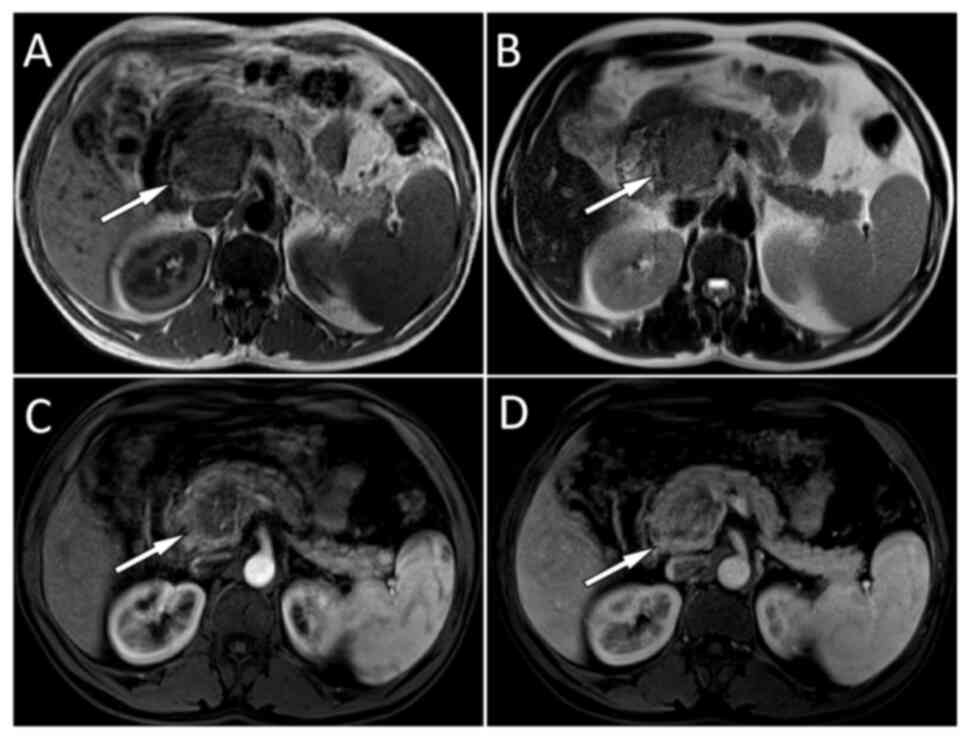

Nesidioblastosis is a rare cause of hyperinsulinemic hypoglycemia in adults and its clinical features are similar to those of insulinoma with recurrent hypoglycemic attacks. The present study reports the case of a 48‑year‑old man who visited the Affiliated Hospital of Zunyi Medical University (Zunyi, China) with a 5‑year history of recurrent hypoglycemic symptoms such as dizziness and palpitations. Abdominal magnetic resonance imaging (MRI) showed a mass of ~1.2x1.0 cm in the head of the pancreas, which was suspected to be an insulinoma. For confirmation, the patient underwent both fluorine‑18‑fluorodeoxyglucose (18F‑FDG) and gallium‑68‑labeled 1,4,7,10‑tetraazacyclododecane‑1,4,7,10‑teraacetic acid‑d‑Phel‑Tyr3‑Thr8‑OC (68Ga‑DOTATATE) positron emission tomography/computed tomography (PET/CT), which showed a moderately increased uptake of 18F‑FDG but no uptake of 68Ga‑DOTATATE in the corresponding lesion. The patient subsequently underwent surgery to remove the lesion, which was pathologically confirmed as a pancreatic nesidioblastosis. This case showed that nesidioblastosis should be considered a differential diagnosis for insulinoma and that dual nuclear tracer PET/CT imaging is helpful for differentiating between the two. If conventional imaging techniques such as ultrasound, CT and MRI cannot identify the cause of hypoglycemia in future cases, dual‑nuclide tracer PET/CT imaging should be considered.